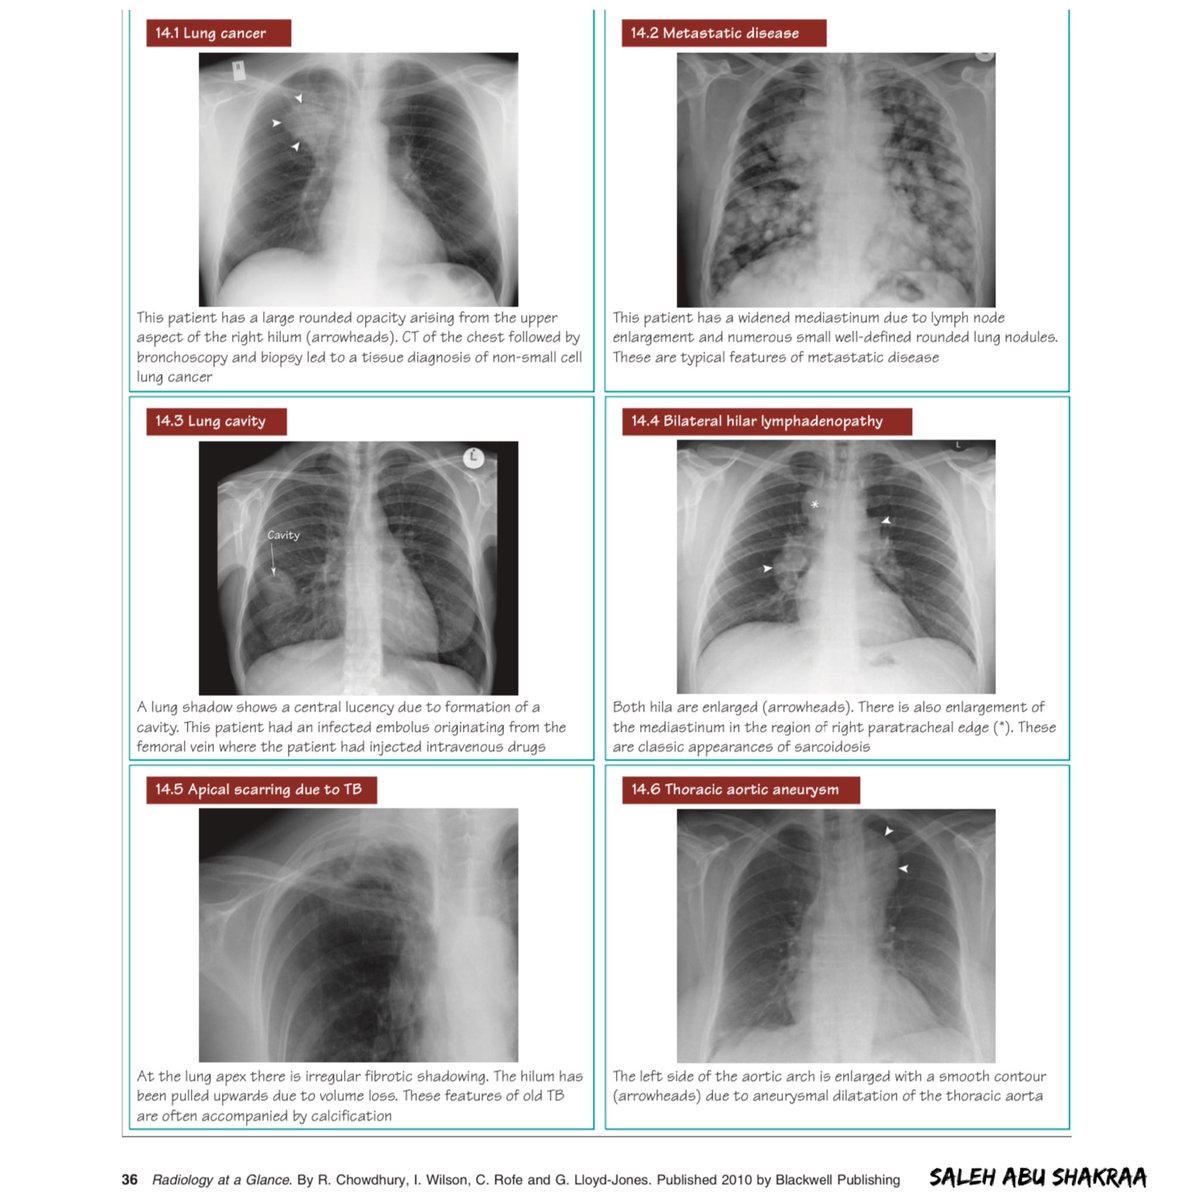

تصوير الصدر بالأشعة السينية من أول الإجراءات التي تخضع لها في حال اشتباه إصابتك بمرض في القلب أو الرئة لا سمح الله

هام جدا☢️

الأمراض الصدرية وكيفية تمييزها على صور الأشعة الأشعة السينية 👇🏼

CXR classic cases